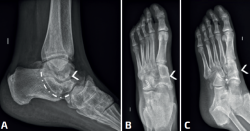

También pueden observarse entre el astrágalo y el escafoides, entre el calcáneo y el cuboides, o entre múltiples huesos del tarso(27) (Figura 2).

mact.1701.fs2403003-figura2.png

Figura 2. Coalición múltiple. Radiografías A: lateral; B: anteroposterior; C: oblicua. Se aprecian coaliciones (flechas blancas): subastragalina (A) y escafocuneanas (B y C). C-sign: línea discontinua. Flecha vacía B: un cuello astragalino afinado, una sobrecobertura del escafoides lateral. Asterisco C: signo del oso hormiguero invertido

Los otros tipos de coalición son raros, representando menos del 10%. Algunas se verán fácilmente en las radiografías. Otras se detectarán como consecuencia de un estudio más profundo tras nuestro diagnóstico de sospecha. Se han descrito coaliciones en la faceta subastragalina posterior, entre el cuboides-escafoides(54), entre el astrágalo-escafoides(55,56,57), el escafoides y los cuneiformes(58), el calcáneo-cuboides(59) y entre múltiples huesos que, en general, se ven fácilmente en las radiografías(22,60,61,62) (Figura 2).